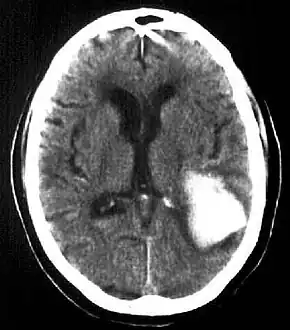

CT scan shows a very large intraparenchymal haemorrhage with mass effect and occupying most of the right frontal lobe -

Intraparenchymal hemorrhage -

CT-scan of intraparenchymal hemorrhage

Computed tomography (CT scan): A CT scan may be normal if it is done soon after the onset of symptoms. A CT scan is the best test to look for bleeding in or around your brain. In some hospitals, a perfusion CT scan may be done to see where the blood is flowing and not flowing in your brain.